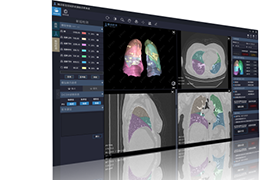

工作流智能。

在这里,先进的智能功能自动执行手动任务和工作流程步骤,以简化流程,提高技术人员工作效率,节省时间和金钱,并增强患者护理。

自动化设备定位和患者姿势确认可优化放射科技师的效率并加快工作流程。

自动技术选择可改善影像一致性并支持辐射剂量控制。

通过任务自动化功能改进感染控制,使放射科技师不再与潜在感染患者直接接触。